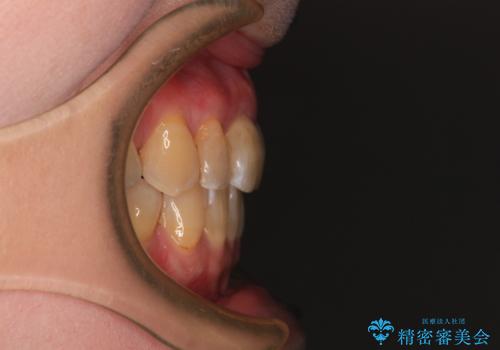

- 口元の突出感を気にして来院された患者様です。

上下前歯が著しく前突している状態であったので、上下左右の小臼歯4本を抜歯し、ワイヤー装置にて矯正治療を行うこととしました。

上顎左側は第二小臼歯に大きなむし歯があったため、通常は第一小臼歯を抜歯するところ、イレギュラーに第二小臼歯を抜歯することとしました。